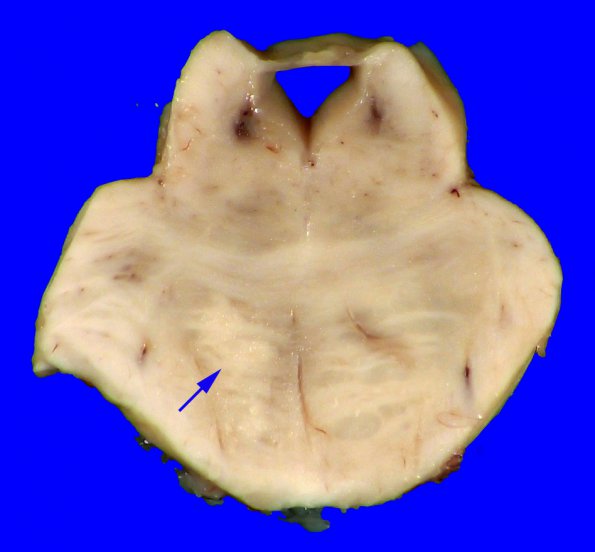

The lesion in the basis pontis (arrow) could represent a primary pontine lesion or represent tract degeneration of the left corticospinal tract resulting from more rostral injury.